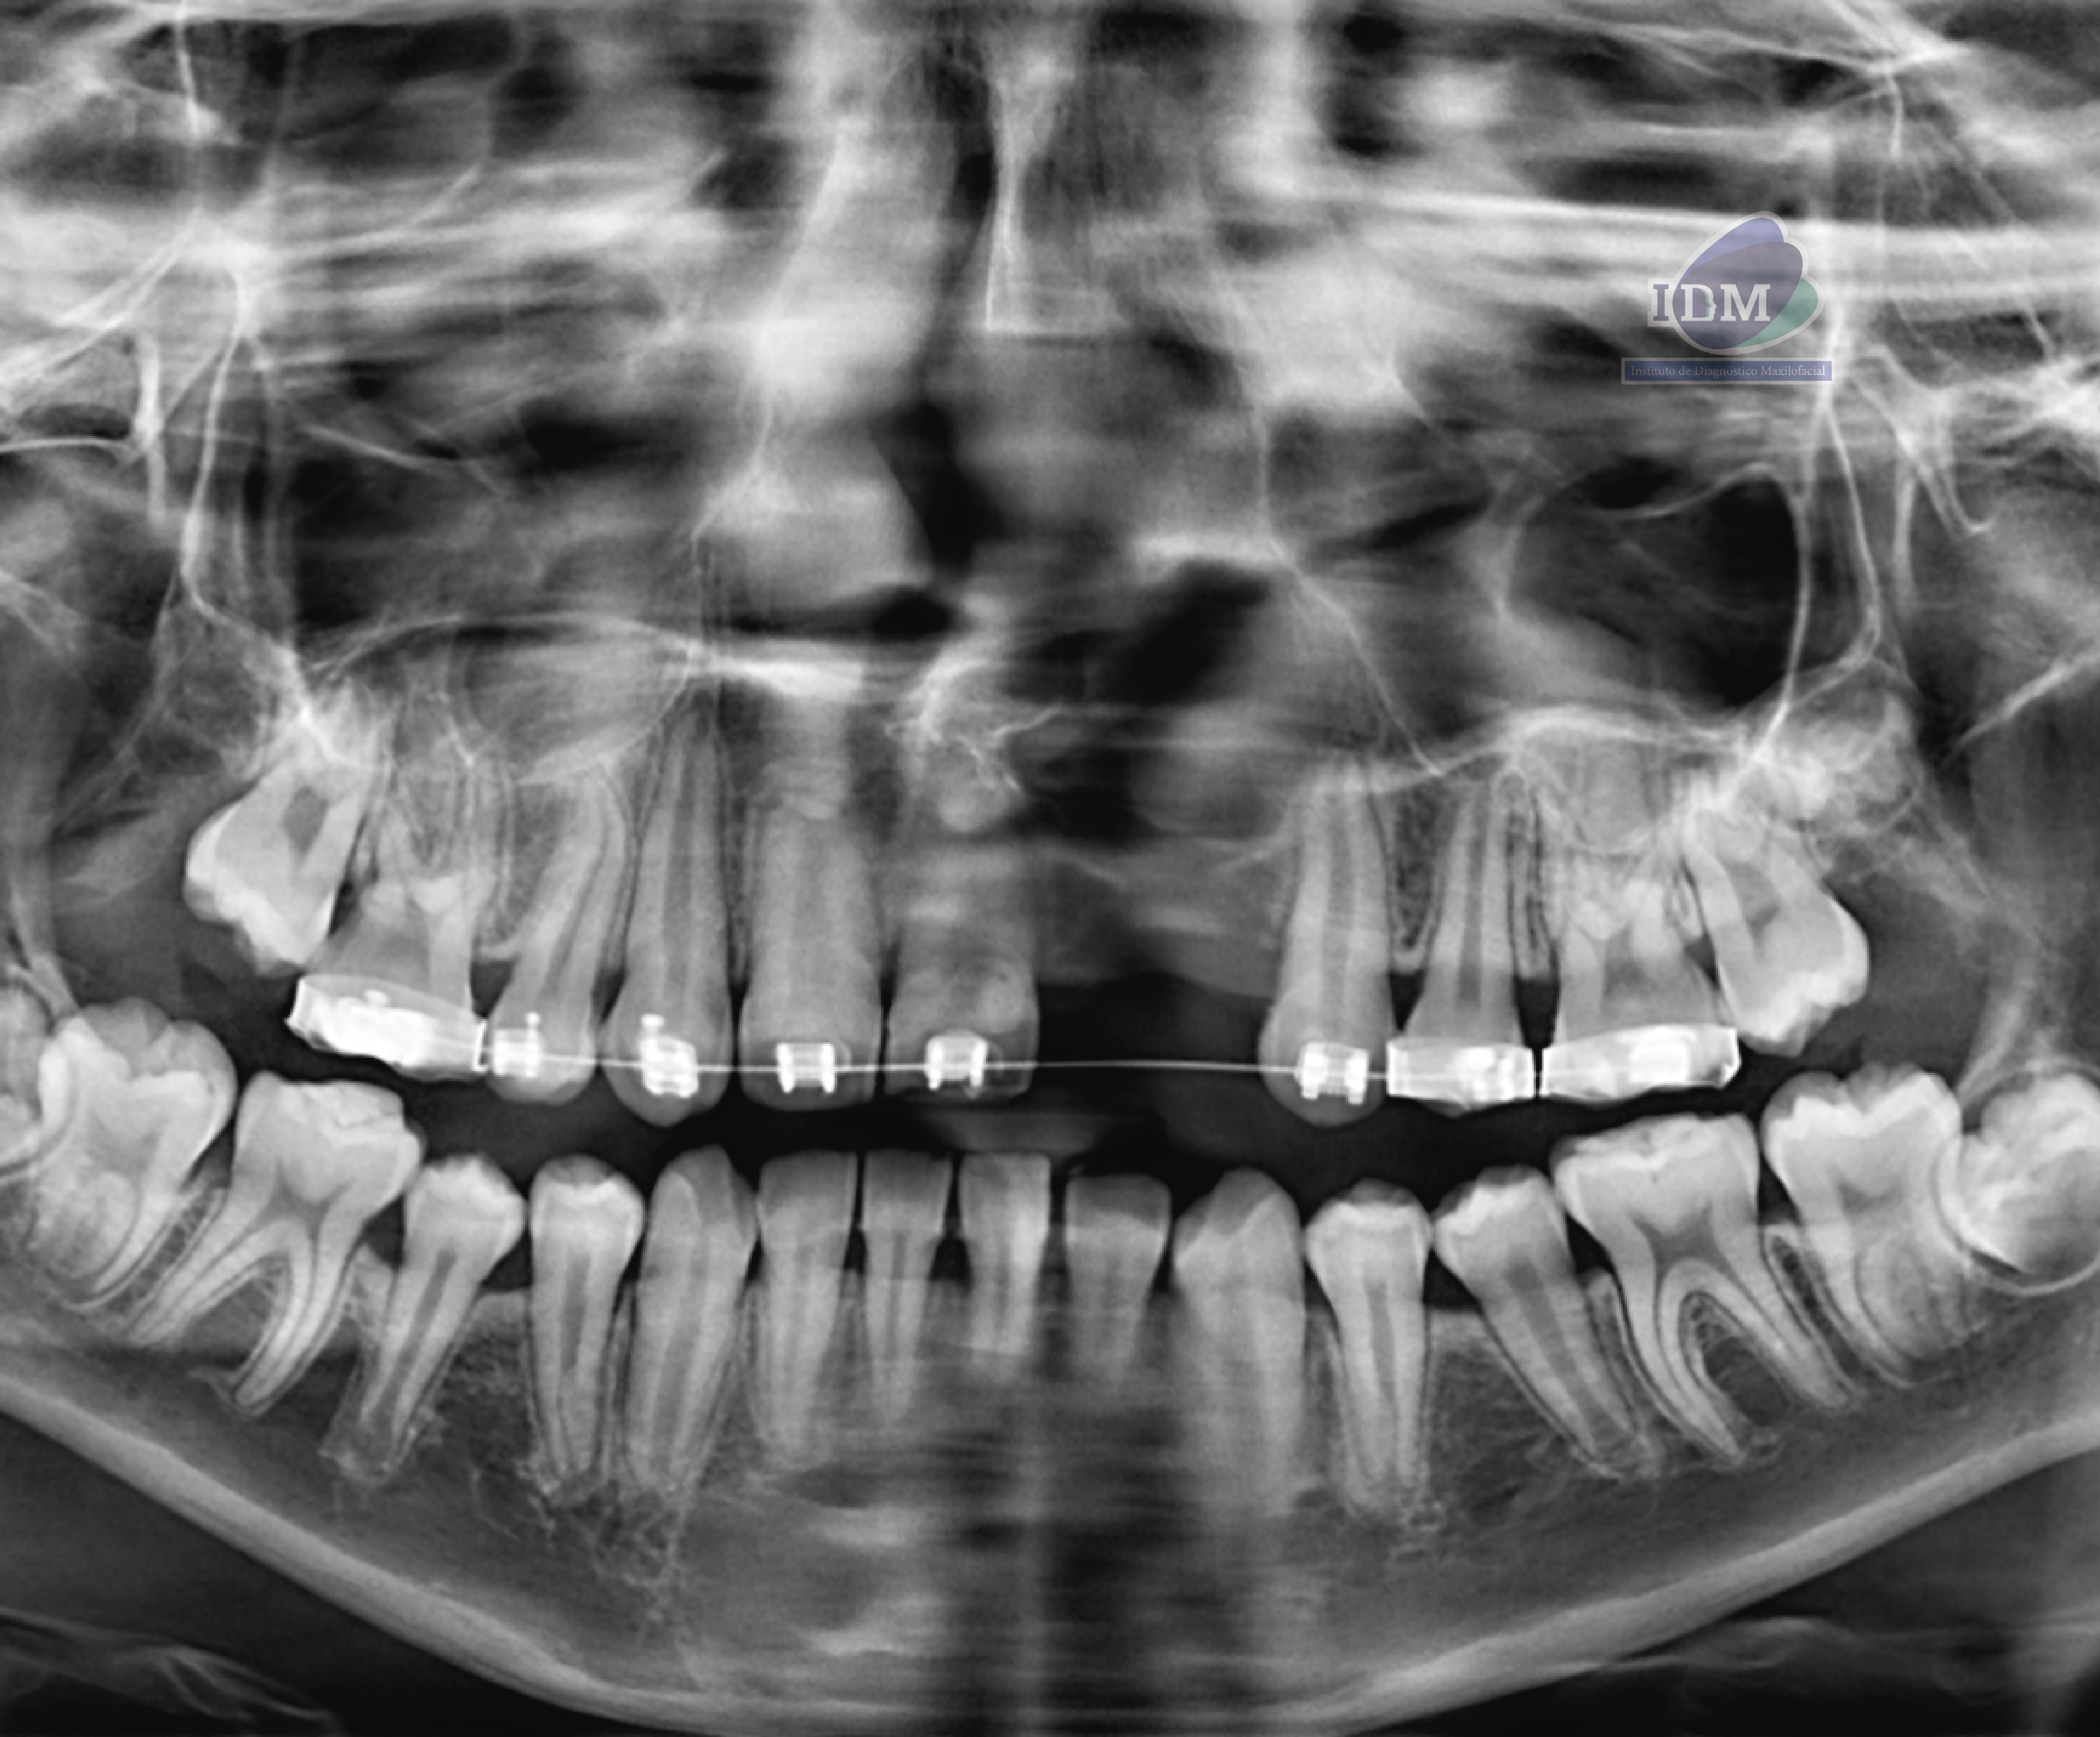

En la radiografía panorámica (Figura 1), se observa neumatización de senos maxilares, defecto óseo en zona anterior izquierda de maxilar superior, ausencia de piezas 22 y 23; además de la aparatología ortodóntica en piezas del maxilar superior.

Radiografia Panorámica